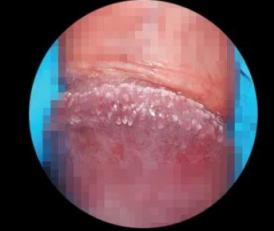

二、主要症状:尖锐湿疣(长什么样)

形态:菜花状、乳头状、鸡冠状、颗粒状

颜色:粉红、肤色、灰白

质地:柔软,触碰易出血

应大哥们要求,上点图片给大家

大家可以看看这些分别 是哪个部位的